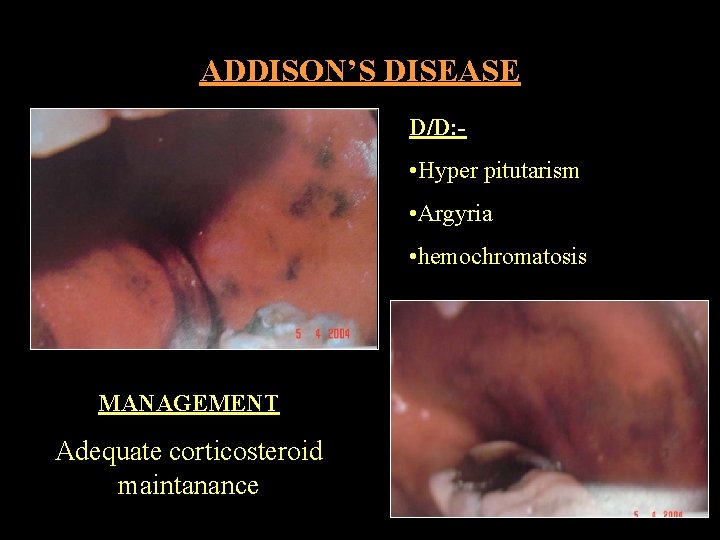

ADDISON’S DISEASE CAUSES CLINICAL FEATURES • Chr Adrenal insufficiency • Skin & MM pigmentation • Bilateral adrenocortical • Cheek /Gingiva /Tongue /Lips destruction TB / fungal • Nausea/ Vomiting/ Diarrhea & Anemia • Bilateral tumor metastasis • Bluesh black/ pale brown/ deep • Leukemic infiltration chocolate • Amyloidosis • Skin Bronze color

ADDISON’S DISEASE D/D: - • Hyper pitutarism • Argyria • hemochromatosis MANAGEMENT Adequate corticosteroid maintanance